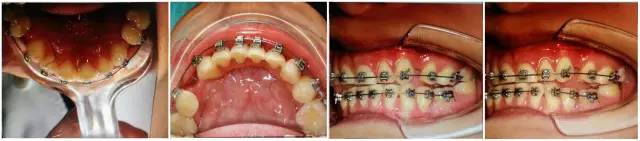

口內(nèi)情況,如以下照片所示:

640.jpg

您是否首先會想到,患者的牙齒是受外力撞擊引起的牙周膜急性創(chuàng)傷?或是(牙合)創(chuàng)傷引起?如果是創(chuàng)傷,這種創(chuàng)傷是如何形成的呢?權老師提示一,患者并無外傷史,進食很小心;提示二,從口內(nèi)照片可得知患者前牙無接觸,(牙合)創(chuàng)傷從何而來呢?

群里多位同仁已經(jīng)發(fā)現(xiàn)了它的不和諧之處,劉坦,劉曉強等多位醫(yī)生先后發(fā)現(xiàn):患者前伸(牙合)后牙有干擾。其他同仁也同時提出或需要進行適當?shù)恼{(diào)(牙合),或使用后牙(牙合)墊抬高后牙咬合,方能解決急性創(chuàng)傷。仔細看口內(nèi)的照片,從咬合的觀點和理論角度出發(fā),您捕捉到什么信息了嗎?